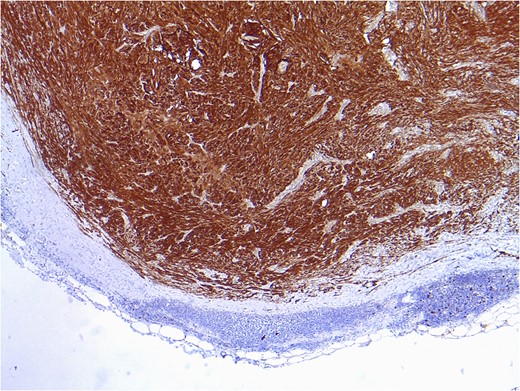

Mesenteric node tumor microscopically constituted by a spindle cell proliferation without atypia, mitosis or necrosis, displacing the normal limphatic tissue toward periphery.

Positive result after immunohistochemical study for vimentin and protein S100, compatible with intranodal schwannoma.